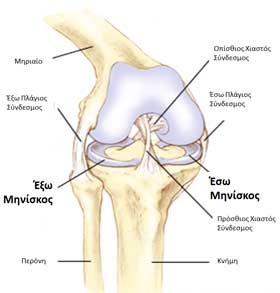

Οι δύο μηνίσκοι είναι ημισεληνοειδούς σχήματος σφήνες που γεμίζουν το κενό μεταξύ των αρθρούμενων οστών, του μηρού και της κνήμης. Οι μηνίσκοι ενισχύουν τη σταθερότητα της άρθρωσης, δημιουργούν πάνω στην επίπεδη κνήμη μια κυπελοειδή δομή στην οποία επικάθεται αρμονικά ο μηρός. Το έσω χείλος του μηνίσκου είναι εξαιρετικά λεπτό, ενώ το έξω είναι παχύτερο δημιουργώντας το σφηνοειδές σχήμα του. Αν αφαιρεθούν οι μηνίσκοι τότε ο κυλινδρικός μηρός μετακινείται απ’ ευθείας στην επίπεδη επιφάνεια της κνήμης.

Οι κακώσεις του έσω μηνίσκου είναι συχνότερες γιατί βρίσκεται σταθερά προσκολλημένος στον έσω πλάγιο σύνδεσμο και τον αρθρικό θύλακο. Ο έξω μηνίσκος είναι πιο στρογγυλός, μικρότερος σε μέγεθος και ευκίνητος καθώς δεν προσκολλάται σταθερά ούτε στον έξω πλάγιο σύνδεσμο ούτε και στον αρθρικό θύλακο.

Το πρόσθιο τμήμα του μηνίσκου ονομάζεται πρόσθιο κέρας, ενώ το οπίσθιο, οπίσθιο κέρας. Το κεντρικό τμήμα του μηνίσκου καλείται σώμα.